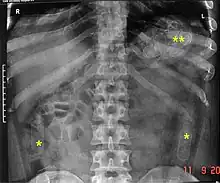

Routine detection of the smuggled packets is extremely difficult, and many cases come to light because a packet has ruptured or because of intestinal obstruction. Unruptured packets may sometimes be detected by rectal or vaginal examination, but the only reliable way is by X-ray of the abdomen. Hashish appears denser than stool, cocaine is approximately the same density as stool, while heroin looks like air.[11][12]

Dx by: Abdominal radiograph, physical evidence of packet, exploratory laparotomy to remove additional packets, sigmoidoscopy.... These were found INSIDE the patient's bowel.... Cocaine packets recovered in the Emergency Department from rectal cavity of patient. Cocaine is stuffed into latex glove fingers and tied. Condoms may also be used - but are more expensive.